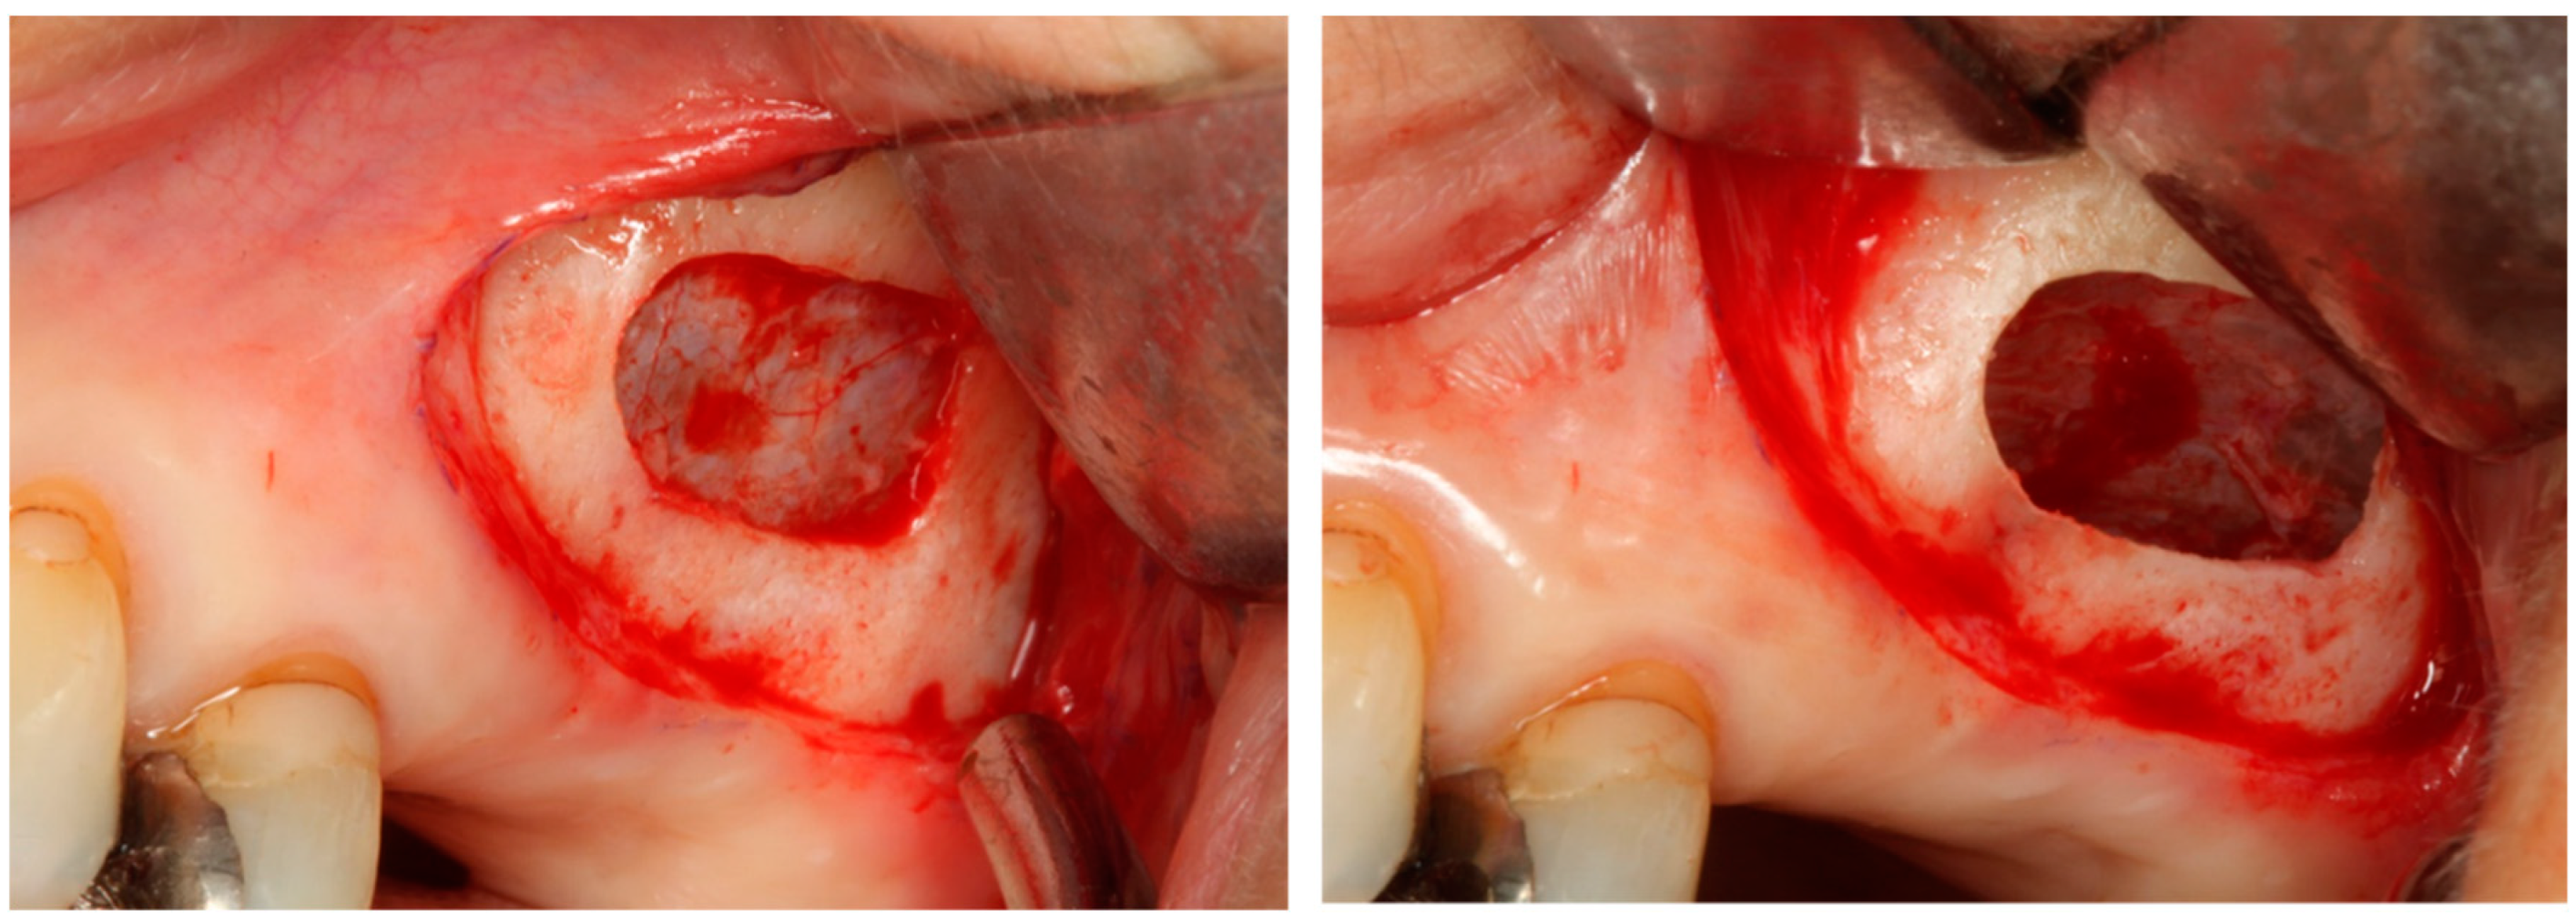

4.3. Sinus Augmentation (Lateral Approach/Crestal Approach)

4.3.1. Relationship between Early Implant Failure and Sinus Augmentation

4.3.2. Selection of the Graft Material in Sinus Augmentation